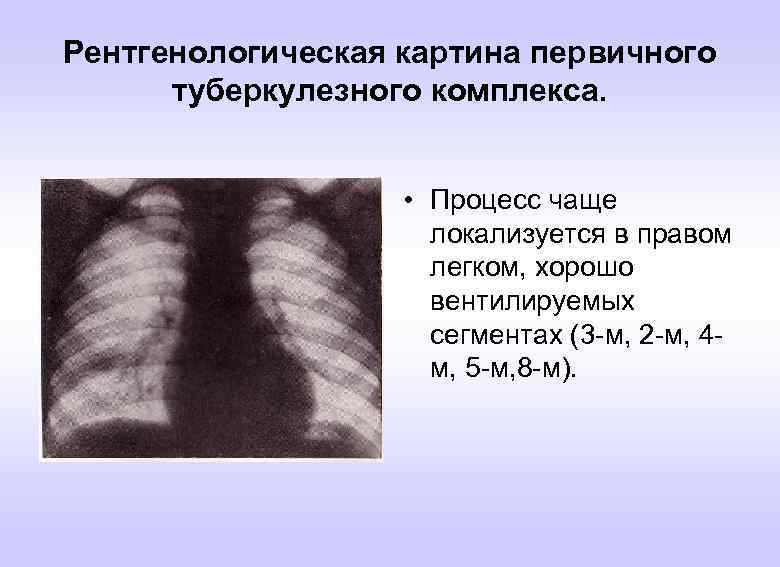

Симптомы и лечение инфильтративного туберкулеза легких

Раздел: Снимки-откровения